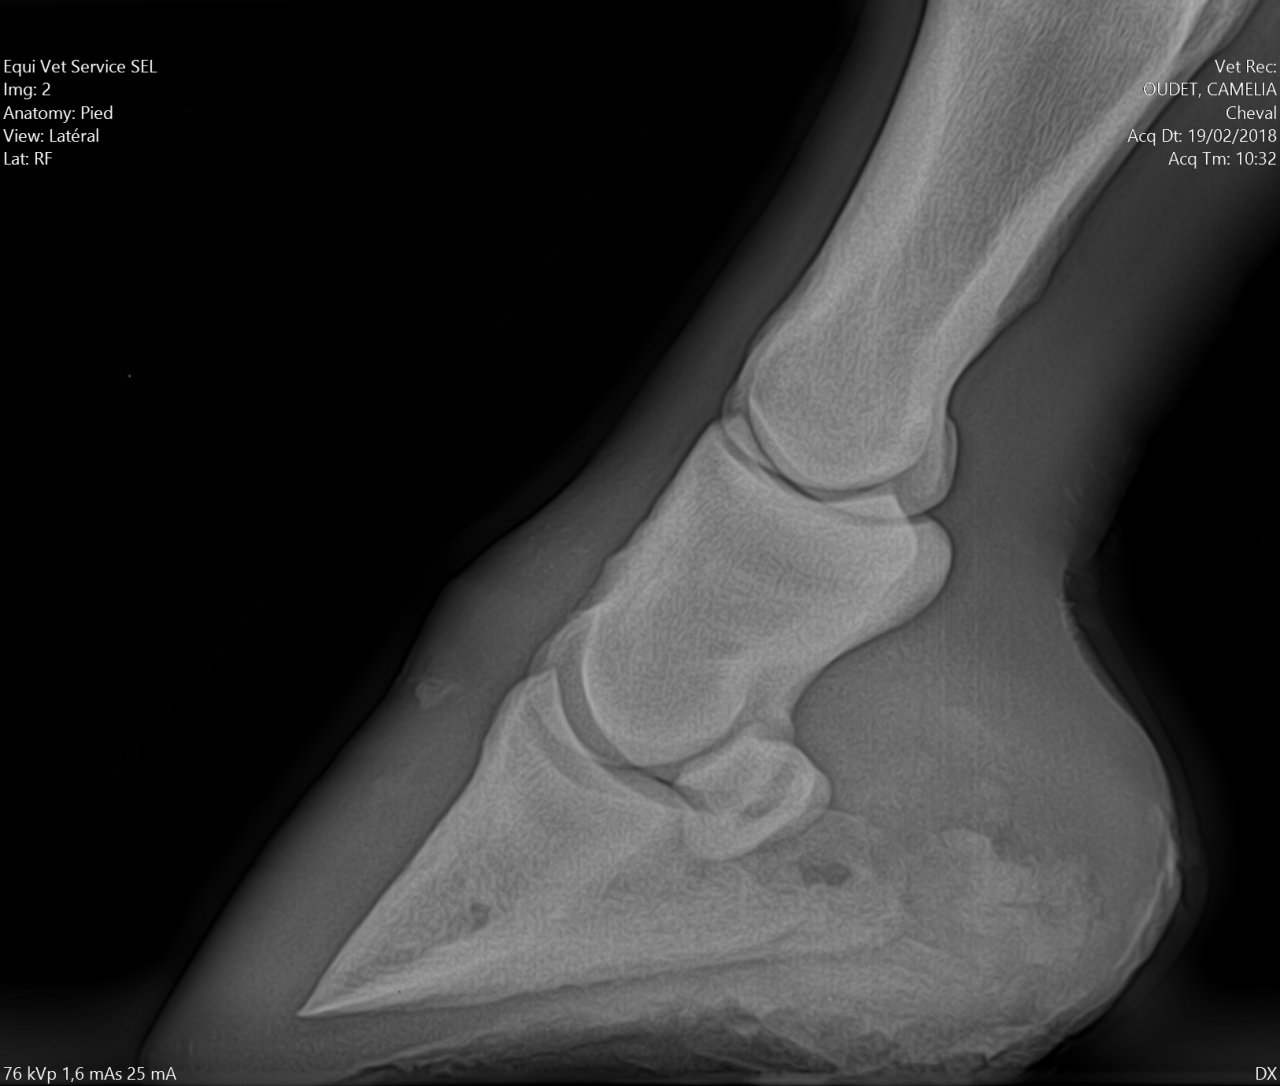

| Dire merci | Alors pour les fers, je ne suis pas une ayatollah du pieds nus, donc je l'ai évoqué avec la véto. Selon elle à ce stade, ça ferait plus de mal que de bien, pour les raisons suivantes : - jument confortable au pré, puisque terrains bien mous en ce moment - difficulté à ferrer vu ce qu'il "reste de pied", elle pense que ça va être un calvaire pour la jument de clouer - si jamais c'est un soucis de vascularisation, ça va plutôt amplifer le soucis Concernant les PHW, justement avec Kaline on était passé à une orthopédie à base de PHW, parce que pas moyen de faire tenir des fers compensés en talon dans la boue. Après ça dépend beaucoup de la locomotion du cheval, mais vu que Cam' n'est pas une foudre de guerre et que même si le pré est boueux on ne s'enfonce pas tant que ça, je suis plutôt confiante. Pour la biotine je veux bien des infos. Moi on m'a souvent dit que ça rendait l'organisme "paresseux" pour en produire lui même, et que si la flore digestive et les apports nutritionnels sont ok y a pas de raison d'avoir de carence ? J'aurais donc plutôt tendance à agir là dessus ? Les radios en spoilers pour celles et ceux que ça intéresse. Message édité le 19/02/18 à 17:18 |

| Dire merci | Il n’y a aucune sole dessus , tu m’étonnes qu’elle ait mal la jument ... Pour clouer en brochant bas aucun soucis et sinon Coller. Mais le temps que l’inflammation parte ... Tu parles de PHW c’est quoi ? |